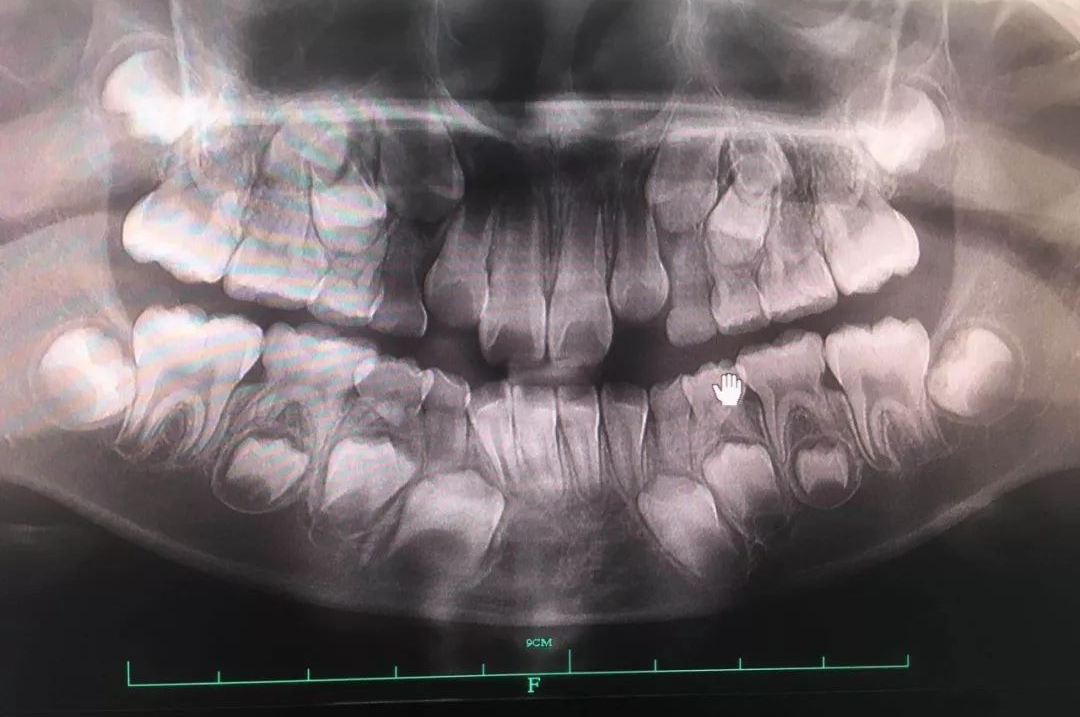

🔎儿童恒牙萌出

X光拍片为什么要等看牙为什么要拍片?非专业人士如何看懂自己的牙片!_https://www.jmylbn.com_新闻资讯_第14张